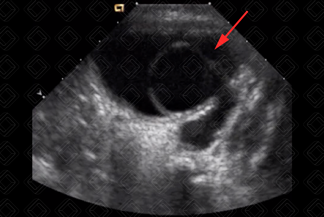

Texto alternativo para a imagem Figura 4. Créditos: Dra. Elazir Mota - Rio de Janeiro/RJ

Descrição das figuras 3 e 4: Ureterocele no assoalho vesical à esquerda (seta vermelha). Na foto de baixo, observamos que ela está relacionada à duplicidade pieloureteral completa, com pólo superior do rim esquerdo displásico.

• Ultrassonografia do aparelho urinário: Imagem arredondada, anecoica, sem fluxo ao Doppler colorido na topografia do óstio ureterovesical acometido, melhor avaliada na fase de enchimento vesical. Atenção! Quando a bexiga estiver muito repleta, a ureterocele pode estar colabada e não ser visualizada (figuras 1, 3 e 4);